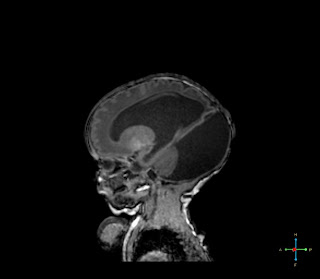

Mellékelek 2 MR felvételt, amit pár naposan készítettek a kicsi buborékfejről...Itt látszik, hogy nem akármennyire üres a kicsi lány feje. ( a sötétszürke a víz) És ennek ellenére így fejlődik!!!!Mindenki döntse el magában, hogy csoda történt, történik,  vagy sem!!!:-)

Hogy most mi van a buksiban, nem tudom, azóta nem csináltak róla MR-t, hála a 2 óriási kutacsának. Innen kukucskálnak be a buksiba ultrahanggal. A shunt műtétek óta a ciszta jóval kisebb lett, a kamra tágulatok is mentek össze. Az agyállomány meg szépen növekszik...Ha tényleg ennyire semmi gond nem lesz a shuntjével, mint az októberi csere óta, akkor üsse-kő...Legyen shunt-ös gyerek. Majd nem kap mágneses játékot..Végül is ez a csoda kis szerkezet mentette meg az életét.